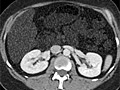

Computed Tomography (CT) Scan of the Body

Computed Tomography (CT) Scan of the BodySkip to the navigationTest OverviewA computed tomography (CT) scan uses

X-rays to make detailed pictures of structures inside

of the body. During the test, you will lie on a table that is

attached to the CT scanner, which is a large doughnut-shaped machine. The CT

scanner sends X-rays through the body area being studied. Each rotation of the

scanner provides a picture of a thin slice of the

organ or area. All of the pictures are saved as a

group on a computer. They also can be printed. In some cases, a